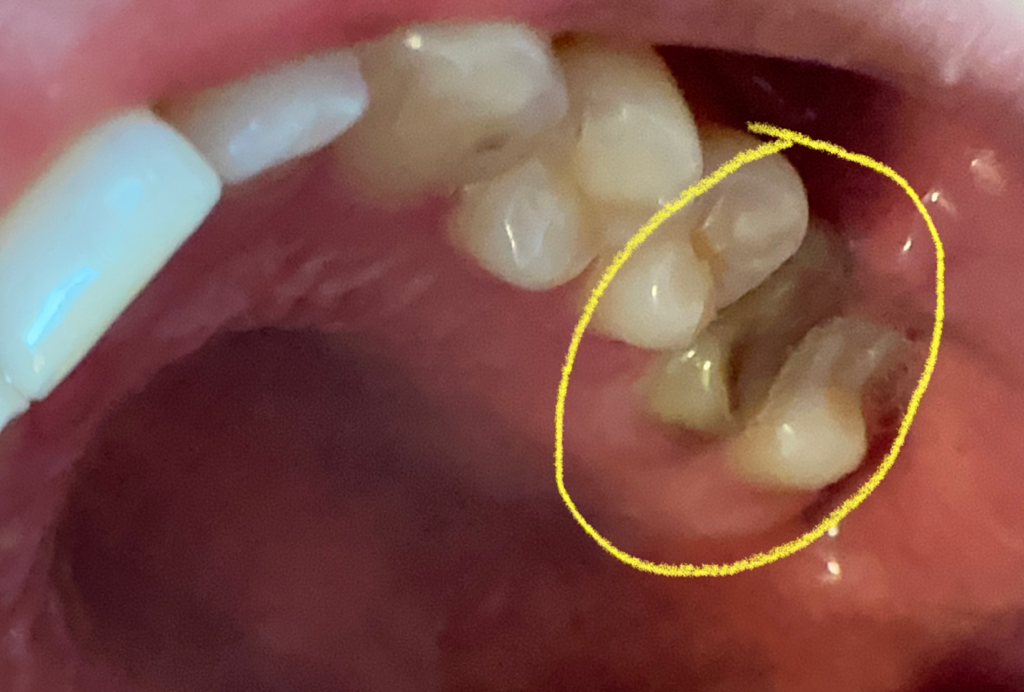

신경치료하고 방치했는데 이빨이 검해졌어요

19년도에 신경치료끝나고

크라운만 씌우면 되는 상황에서

크라운 씌우지않고 방치해뒀더니

저렇게 색깔이 변질되어있습니다.

사진으로 봤을때 상황이 심각할까요?

• 1번 째 사진